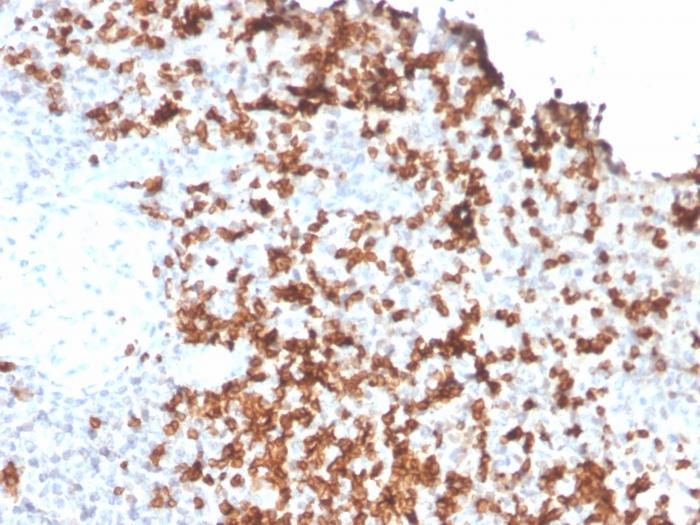

Granzyme B is a member of the granule serine protease family stored specifically in NK cells or cytotoxic T cells. Cytolytic T lymphocytes (CTL) and natural killer (NK) cells share the ability to recognize, bind, and lyse specific target cells. They are thought to protect their host by lysing cells bearing on their surface 'nonself' antigens, usually peptides or proteins resulting from infection by intracellular pathogens. Granzyme B is crucial for the rapid induction of target cell apoptosis by CTLs in the cell-mediated immune response. Granzyme B is useful as a marker in the identification of NK/T-cell lymphomas. High percentages of cytotoxic T-cells have been shown to be an unfavorable prognostic indicator in Hodgkin's Disease. Primary antibodies are available purified, or with a selection of fluorescent CF® Dyes and other labels. CF® Dyes offer exceptional brightness and photostability. Note: Conjugates of blue fluorescent dyes like CF®405S and CF®405M are not recommended for detecting low abundance targets, because blue dyes have lower fluorescence and can give higher non-specific background than other dye colors.

Positive Control

A431 cells. Human tonsil, spleen or Hodgkin' s Lymphoma tissue (IHC).